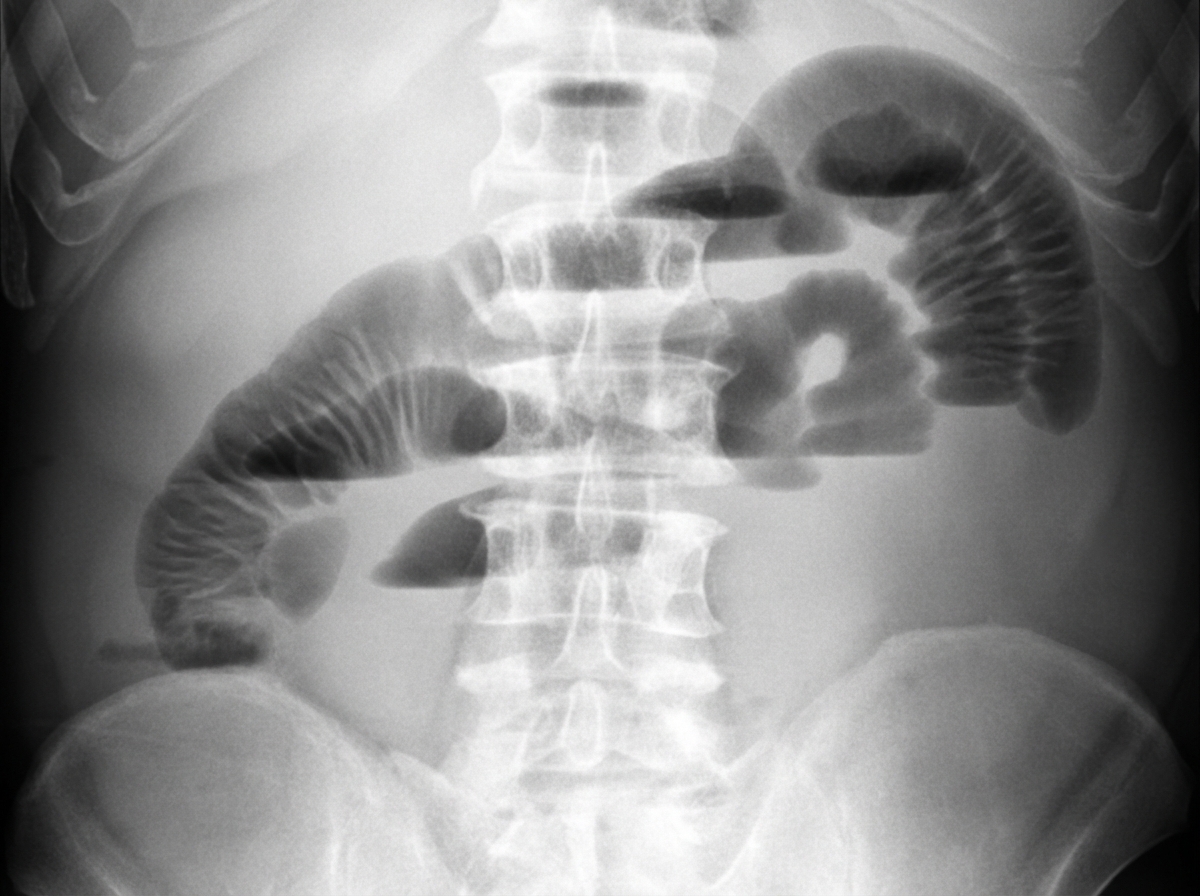

A 24-year-old man presents to the emergency department with a 12-hour history of intermittent, crampy abdominal pain and five episodes of vomiting. He denies any rectal bleeding. On examination, his abdomen is distended with absent bowel sounds. Per-rectal examination is normal. An abdominal X-ray reveals findings suggestive of a specific condition. Based on the X-ray findings, which of the following statements are true?

Explanation: ***Haustra are not visible*** - In **small bowel obstruction**, haustra are absent because haustra are characteristic features of the **large bowel** (colon), not the small bowel. - The absence of haustra on X-ray helps differentiate **small bowel** from **large bowel obstruction**, making this a key diagnostic feature. *Distribution of intestinal loops is mainly in the center* - While small bowel loops are typically **centrally located**, this distribution can vary and is not as definitive as other radiological features. - **Large bowel** can also occupy central areas, making this feature less reliable for distinguishing small bowel obstruction. *No visible plicae circulares* - **Plicae circulares** (valvulae conniventes) are actually **visible** in small bowel obstruction and are a characteristic feature of the small bowel. - These **mucosal folds** extend across the full width of the small bowel lumen and help identify small bowel on X-ray. *String of beads sign is present* - The **string of beads sign** represents alternating **gas and fluid levels** and can be seen in small bowel obstruction, but it's not consistently present. - This sign is more suggestive than diagnostic and may not be visible in all cases of **small bowel obstruction**.

Explanation: **Explanation:** The diagnosis of intestinal obstruction relies on a combination of clinical assessment and radiological imaging to determine the site, level, and cause of the blockage. 1. **Why Option A is Correct:** * **Plain X-rays (Erect and Supine Abdomen):** These are the initial investigations of choice. The **erect film** is essential to visualize **multiple air-fluid levels** (stepladder pattern) and pneumoperitoneum (gas under the diaphragm). The **supine film** helps identify the distribution of gas, allowing the clinician to differentiate between small bowel (central loops, valvulae conniventes) and large bowel (peripheral loops, haustrations) obstruction. * **Intestinal Barium Meal (Follow-through):** While CT is now the gold standard, a barium meal/follow-through is used in subacute or chronic cases to identify the specific site of obstruction or transit time abnormalities. 2. **Why Other Options are Incorrect:** * **Barium Swallow (Options B, C, and D):** This investigation is specifically designed to evaluate the **esophagus** and the upper part of the stomach. It has no diagnostic value in intestinal obstruction, which typically involves the small or large bowel. Including it in the workup for a suspected distal obstruction is clinically irrelevant. **High-Yield Clinical Pearls for NEET-PG:** * **Gold Standard Investigation:** Contrast-Enhanced CT (CECT) of the abdomen is the most accurate investigation for diagnosing the cause and site of obstruction. * **Classic X-ray Sign:** "String of beads" or "String of pearls" sign is highly suggestive of small bowel obstruction (gas trapped between valvulae conniventes). * **Contraindication:** Barium should **never** be given orally if a complete or large bowel obstruction is suspected, as it can inspissate and worsen the blockage. Gastrografin (water-soluble contrast) is preferred in such cases. * **Cut-off for Air-Fluid Levels:** More than 2–3 fluid levels are considered pathological in an adult.